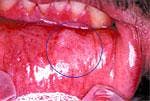

Oral Cancer Lesions

Photos reprinted by permission of CDx Laboratories, Inc.